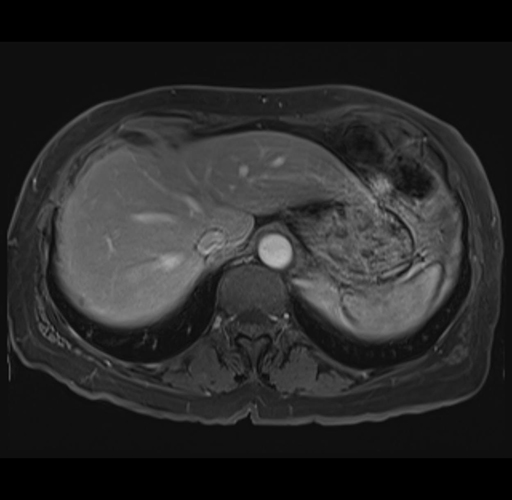

MRI T1